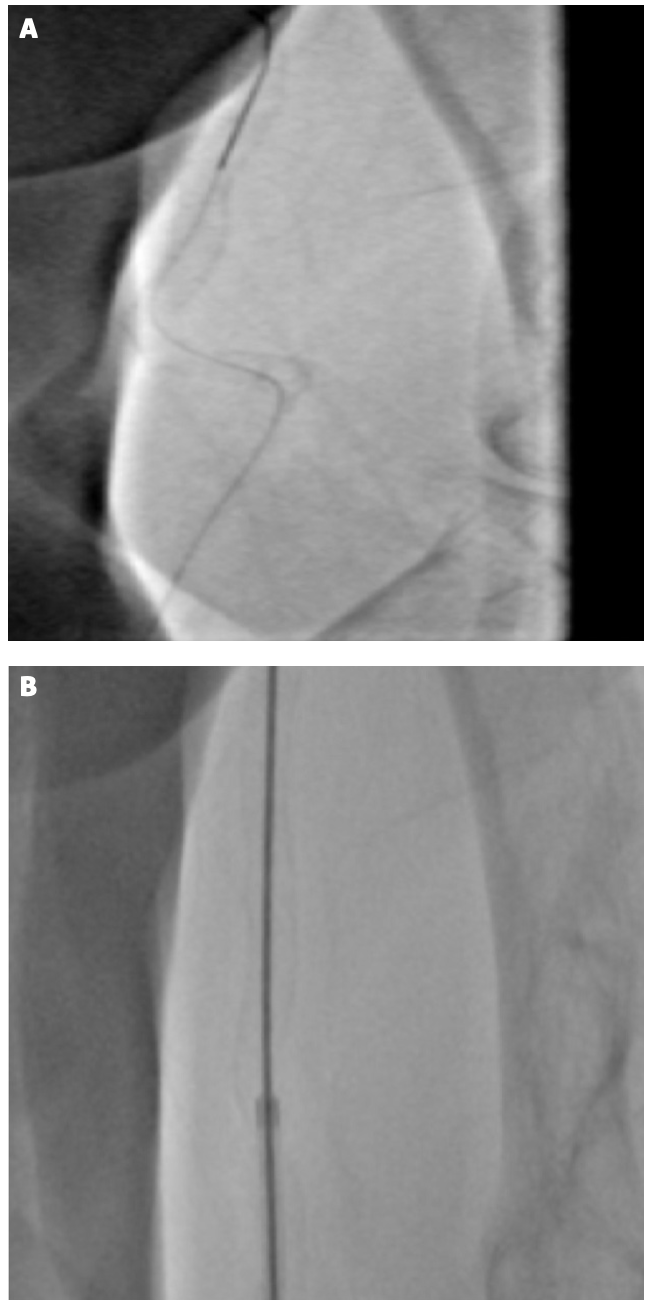

Coronary procedure. For each procedure, we started by carefully positioning the hand before puncturing the proximal radial artery. Specifically, we settle the hand palm in a supine position to achieve hyperextension of the wrist. Then, a standard single anterior vessel wall puncture technique is performed without ultrasound guidance. We performed the puncture in the portion of the distal radial artery at the anatomical snuffbox (Figure 1A), in the dorsal side of the wrist (fovea radialis), limited posteriorly by the edge of the extensor pollicis longus tendon, and anteriorly by the extensor pollicis brevis and abductor pollicis longus tendons. Local anesthesia was performed using a mix of 3 mg of mepivacaine hydrochloride and 1 mg of isosorbide dinitrate injected subcutaneously. The access-site puncture was performed using a 21-gauge bare needle from lateral to medial with an angle of around 35°. After achieving radial artery access, a 5-Fr Radifocus sheath (Terumo) was inserted for the diagnostic angiogram or a 6-Fr sheath was inserted for coronary angioplasty. All patients received a low dose of midazolam, with additional intravenous morphine in case of discomfort. An intra-arterial spasmolytic cocktail with 2 mg of verapamil and 100 μg of nitroglycerin was administered routinely following sheath insertion. A second cocktail with verapamil and nitroglycerin was administered in case of pain during advancement of the catheters. All patients received unfractionated heparin at doses of 50 U/kg for diagnostic catheterization and 100 U/kg for coronary angioplasty. A conventional .035˝ J tip Emerald Wire (Cordis) was positioned in the ascending aorta. In case of difficulties in moving the guide catheter forward, the operator had different options, ie, downsizing the guide catheter, increasing patient sedation, further antispasmolytic mix, or using a balloon-tracking technique. The selection and use of one or more of the mentioned strategies depended on operator choice. In our strategy design, persistent failure prompted us to perform the RTT. At the end of the procedure, we used dedicated devices for achieving artery hemostasis through artery external compression for 2 hours: the TR Band (Terumo) for proximal radial artery and the Prelude Sync (Merit) for distal radial access site.

RailTracking technique description. After achieving access via the proximal or distal radial artery, the placement of a conventional 5-Fr sheath and a J tip .035˝ guidewire was positioned in the ascending aorta (Figure 1A, 1B). The RTT could then be performed as sheathless or not. The 5-Fr sheath was removed and a 6-Fr or 7-Fr guide catheter was preloaded on the .035˝-wire-compatible Railway dilator (Figure 1C, 1D). The system was advanced directly on the wire through the access in the aortic arch (Figure 1E) if a sheathless approach was needed. Alternatively, the RTT could also be performed by inserting the dilator and the guide catheter together through the sheath, leaving the 6-Fr introducer in place. The Railway dilator was pulled out when the guiding catheter reached the ascending aorta, followed by the guide catheter up to the coronary sinus for coronary cannulation. In our practice, when using a 7-Fr guiding catheter, distal RTT was preferred as the first choice in complex coronary. In other cases, the RTT was used more as a bailout strategy in case of complication while advancing the catheters.